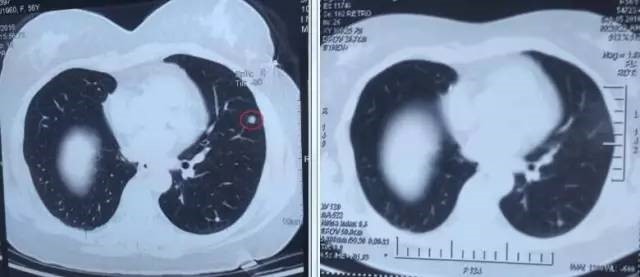

左图红色圈内是A45治疗前三个肺癌病灶,右图为治疗后病灶消失